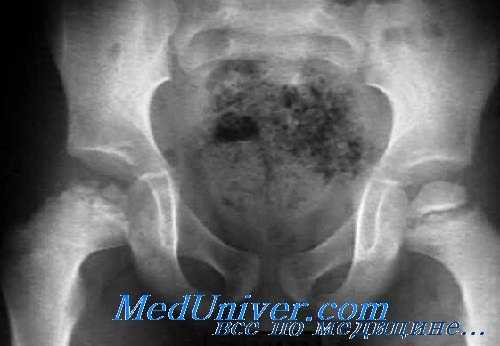

Ранним признаком болезни Легга—Кальве—Пертеса является расширение суставной щели и выбухание мягких тканей над капсулой с минимальным выпотом в суставе. Головка бедренной кости в вертлужной впадине может быть слегка сдвинута латерально. Через несколько недель головка бедра будет выглядеть более плотной, чем остальная кость, с последующей фрагментацией.

Появление фрагментации на спине — признак некроза; врастание новых сосудов стимулирует процесс реабсорбции. Это приводит к уменьшению плотности проксимального конца метафиза из-за усиленной васкуляризации и остеосклероза с расширением и укорочением шейки бедренной кости и увеличением плотности головки.

Стадия фрагментации занимает период от 1 года до 2 лет, вслед за которой наступает фаза регенерации, при которой в эпифизе формируется новая кость и окончательная форма головки варьируется в размере и очертаниях в зависимости от степени сплющивания, происшедшего ранее. В дальнейшем постепенно развиваются явления вторичного остеоартроза.